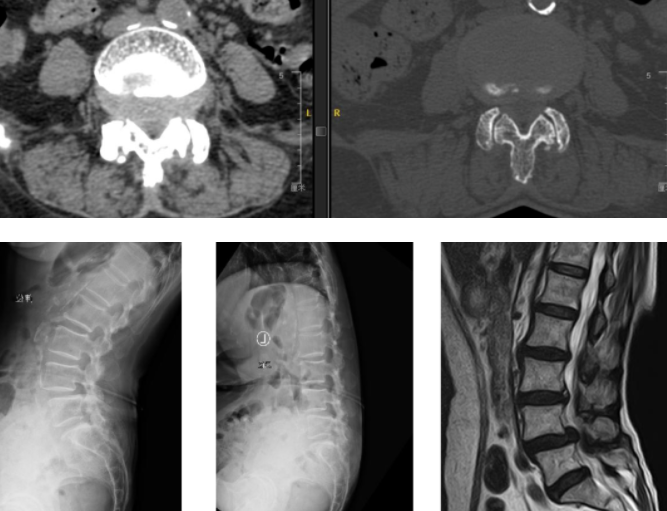

术前资料

入院后,在完善相关检查后王阿姨被诊断为:腰椎管狭窄、腰椎不稳、腰椎间盘突出。随后脊柱外科尚军、张冶手术团队在骨科机器人+3D裸眼显微镜的辅助下,为王阿姨进行了腰椎后路减压+内固定+椎间融合术 (L4/5)。